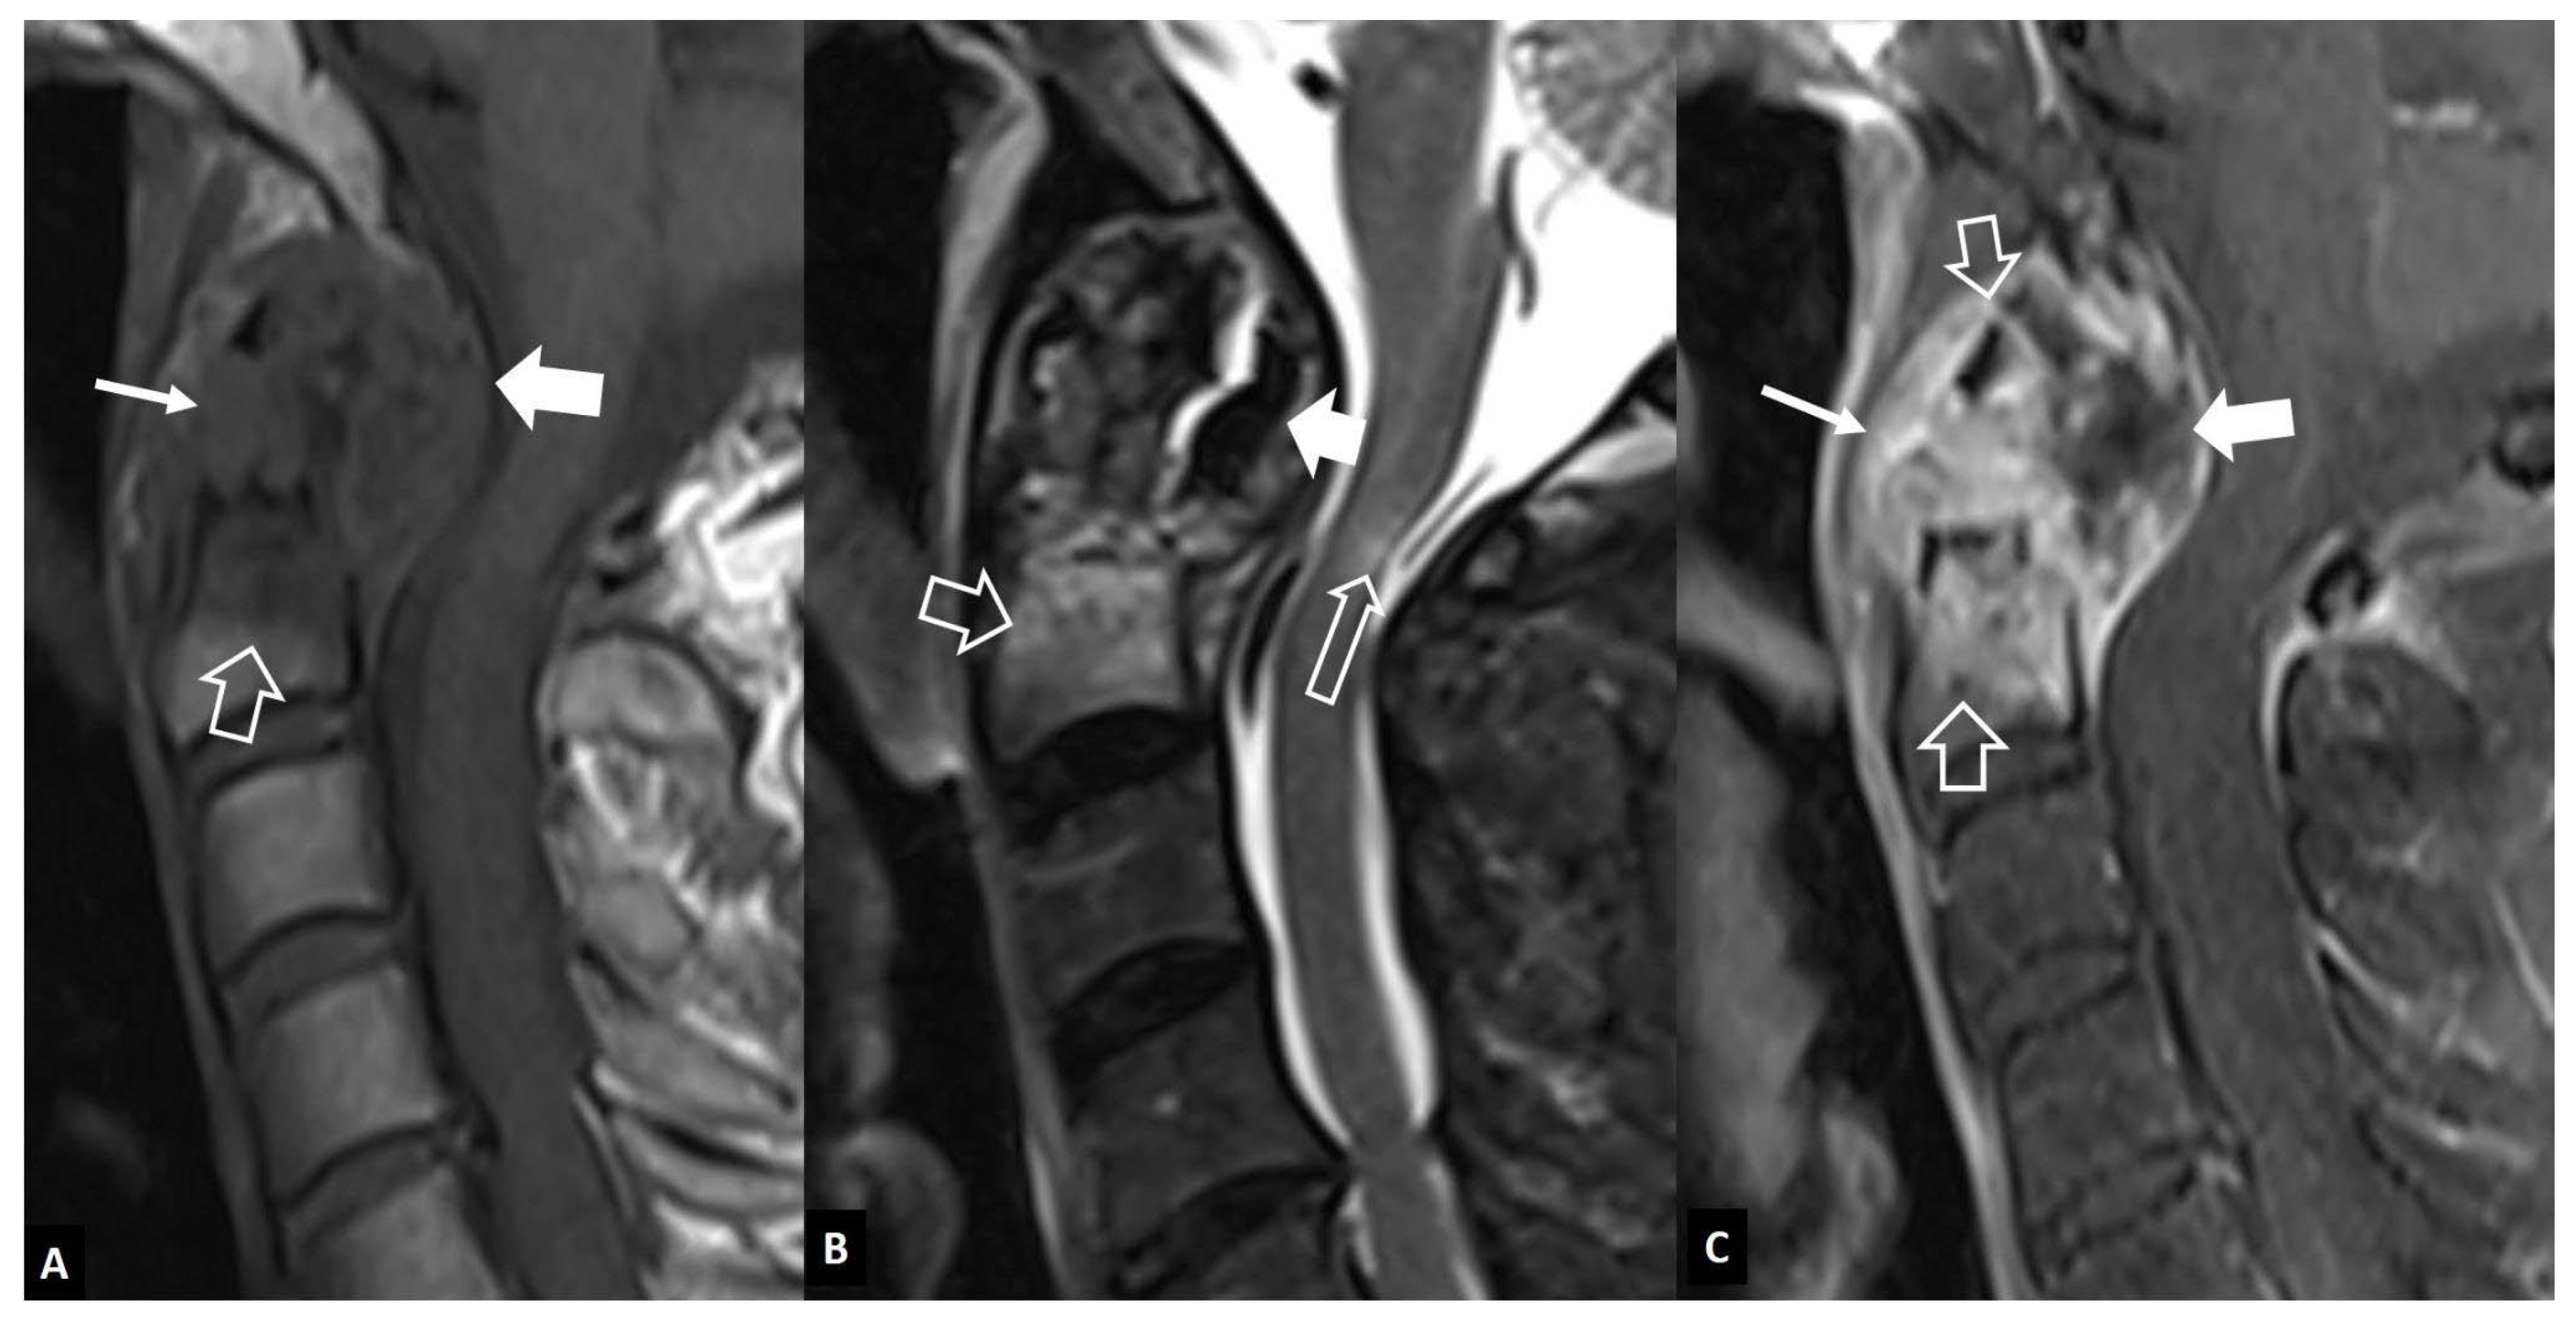

1. a.iii. SAPHO Syndrome

- Andersson O. Rontgenbilden vid spondylarthritis ankylopoetica. 1937.

- Hunter T The spinal complications of ankylosing spondylitis. Semin Arthritis Rheum 1989, 19, 172–182. [CrossRef] [PubMed]

- Kim S-K, Shin K, Song Y, Lee S, Kim T-H Andersson lesions of whole spine magnetic resonance imaging compared with plain radiography in ankylosing spondylitis. Rheumatol Int 2016, 36, 1663–1670. [CrossRef]

- Bennett AN, Rehman A, Hensor EMA, Marzo-Ortega H, Emery P, McGonagle D Evaluation of the diagnostic utility of spinal magnetic resonance imaging in axial spondylarthritis. Arthritis Rheum 2009, 60, 1331–1341. [CrossRef] [PubMed]

- Kabasakal Y, Garrett SL, Calin A The epidemiology of spondylodiscitis in ankylosing spondylitis--a controlled study. Br J Rheumatol 1996, 35, 660–663. [CrossRef] [PubMed]

- Madsen KB, Jurik AG MRI grading method for active and chronic spinal changes in spondyloarthritis. Clin Radiol 2010, 65, 6–14. [CrossRef]

- Park Y-S, Kim J-H, Ryu J-A, Kim T-H The Andersson lesion in ankylosing spondylitis: distinguishing between the inflammatory and traumatic subtypes. J Bone Joint Surg Br 2011, 93, 961–966.